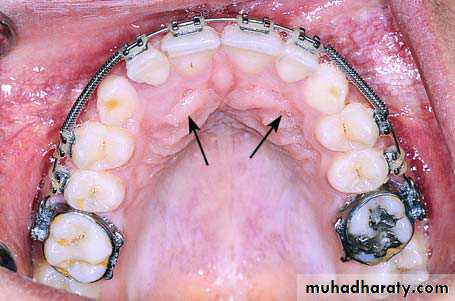

PALATALLY IMPACTED CANINES

The treatment options for the palatally impacted canine include open or closed eruption techniques.After removal of the deciduous teeth, a palatal flap is created, underneath which part of the bone covering the teeth is exposed. A round bur is then used to remove the bone covering the crowns and orthodontic brackets are placed for traction of the teeth into their normal position in the dental arch. The area is then irrigated with saline solution and the flap is closed with interrupted sutures.

Radiograph showing impacted maxillary canines with a palatal localization

Clinical photograph of the area of impaction

Removal of the bone covering the crowns of impacted teeth

Surgical field immediately after exposure of

impacted teeth. Orthodontic brackets have been placed on exposed parts of the crowns of the teethSurgical field after suturing